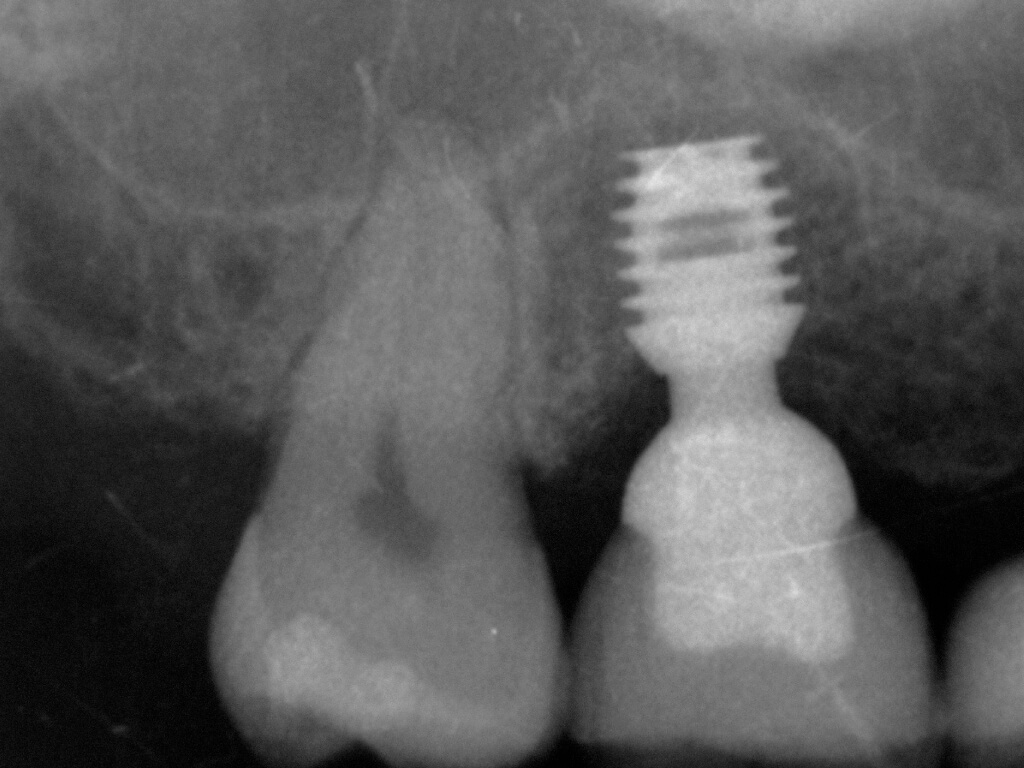

Клінічні кейси спікера: